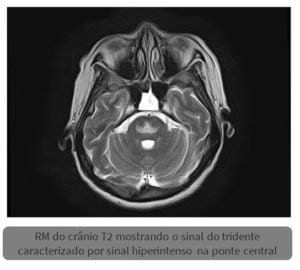

Sinal do tridente na síndrome da desmielinização osmótica